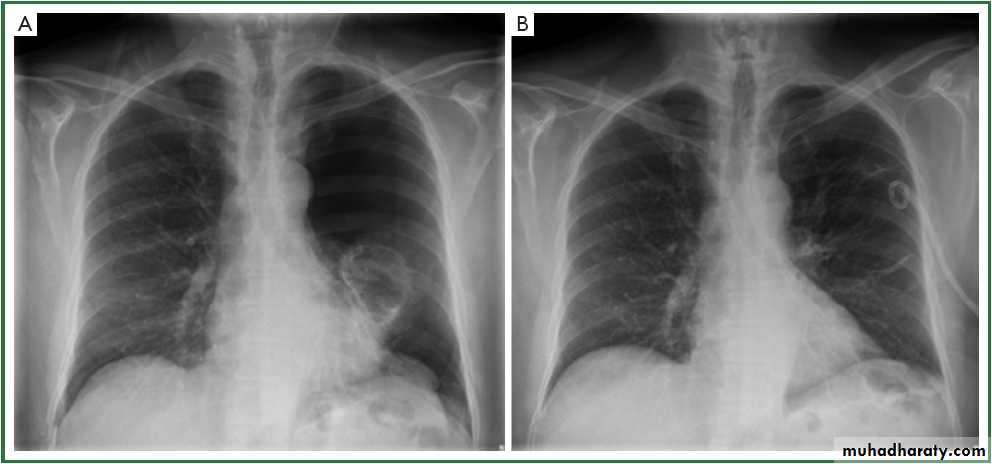

X-ray tension pneumothorax

Pneumothorax

A: before treatment

B: after treatment